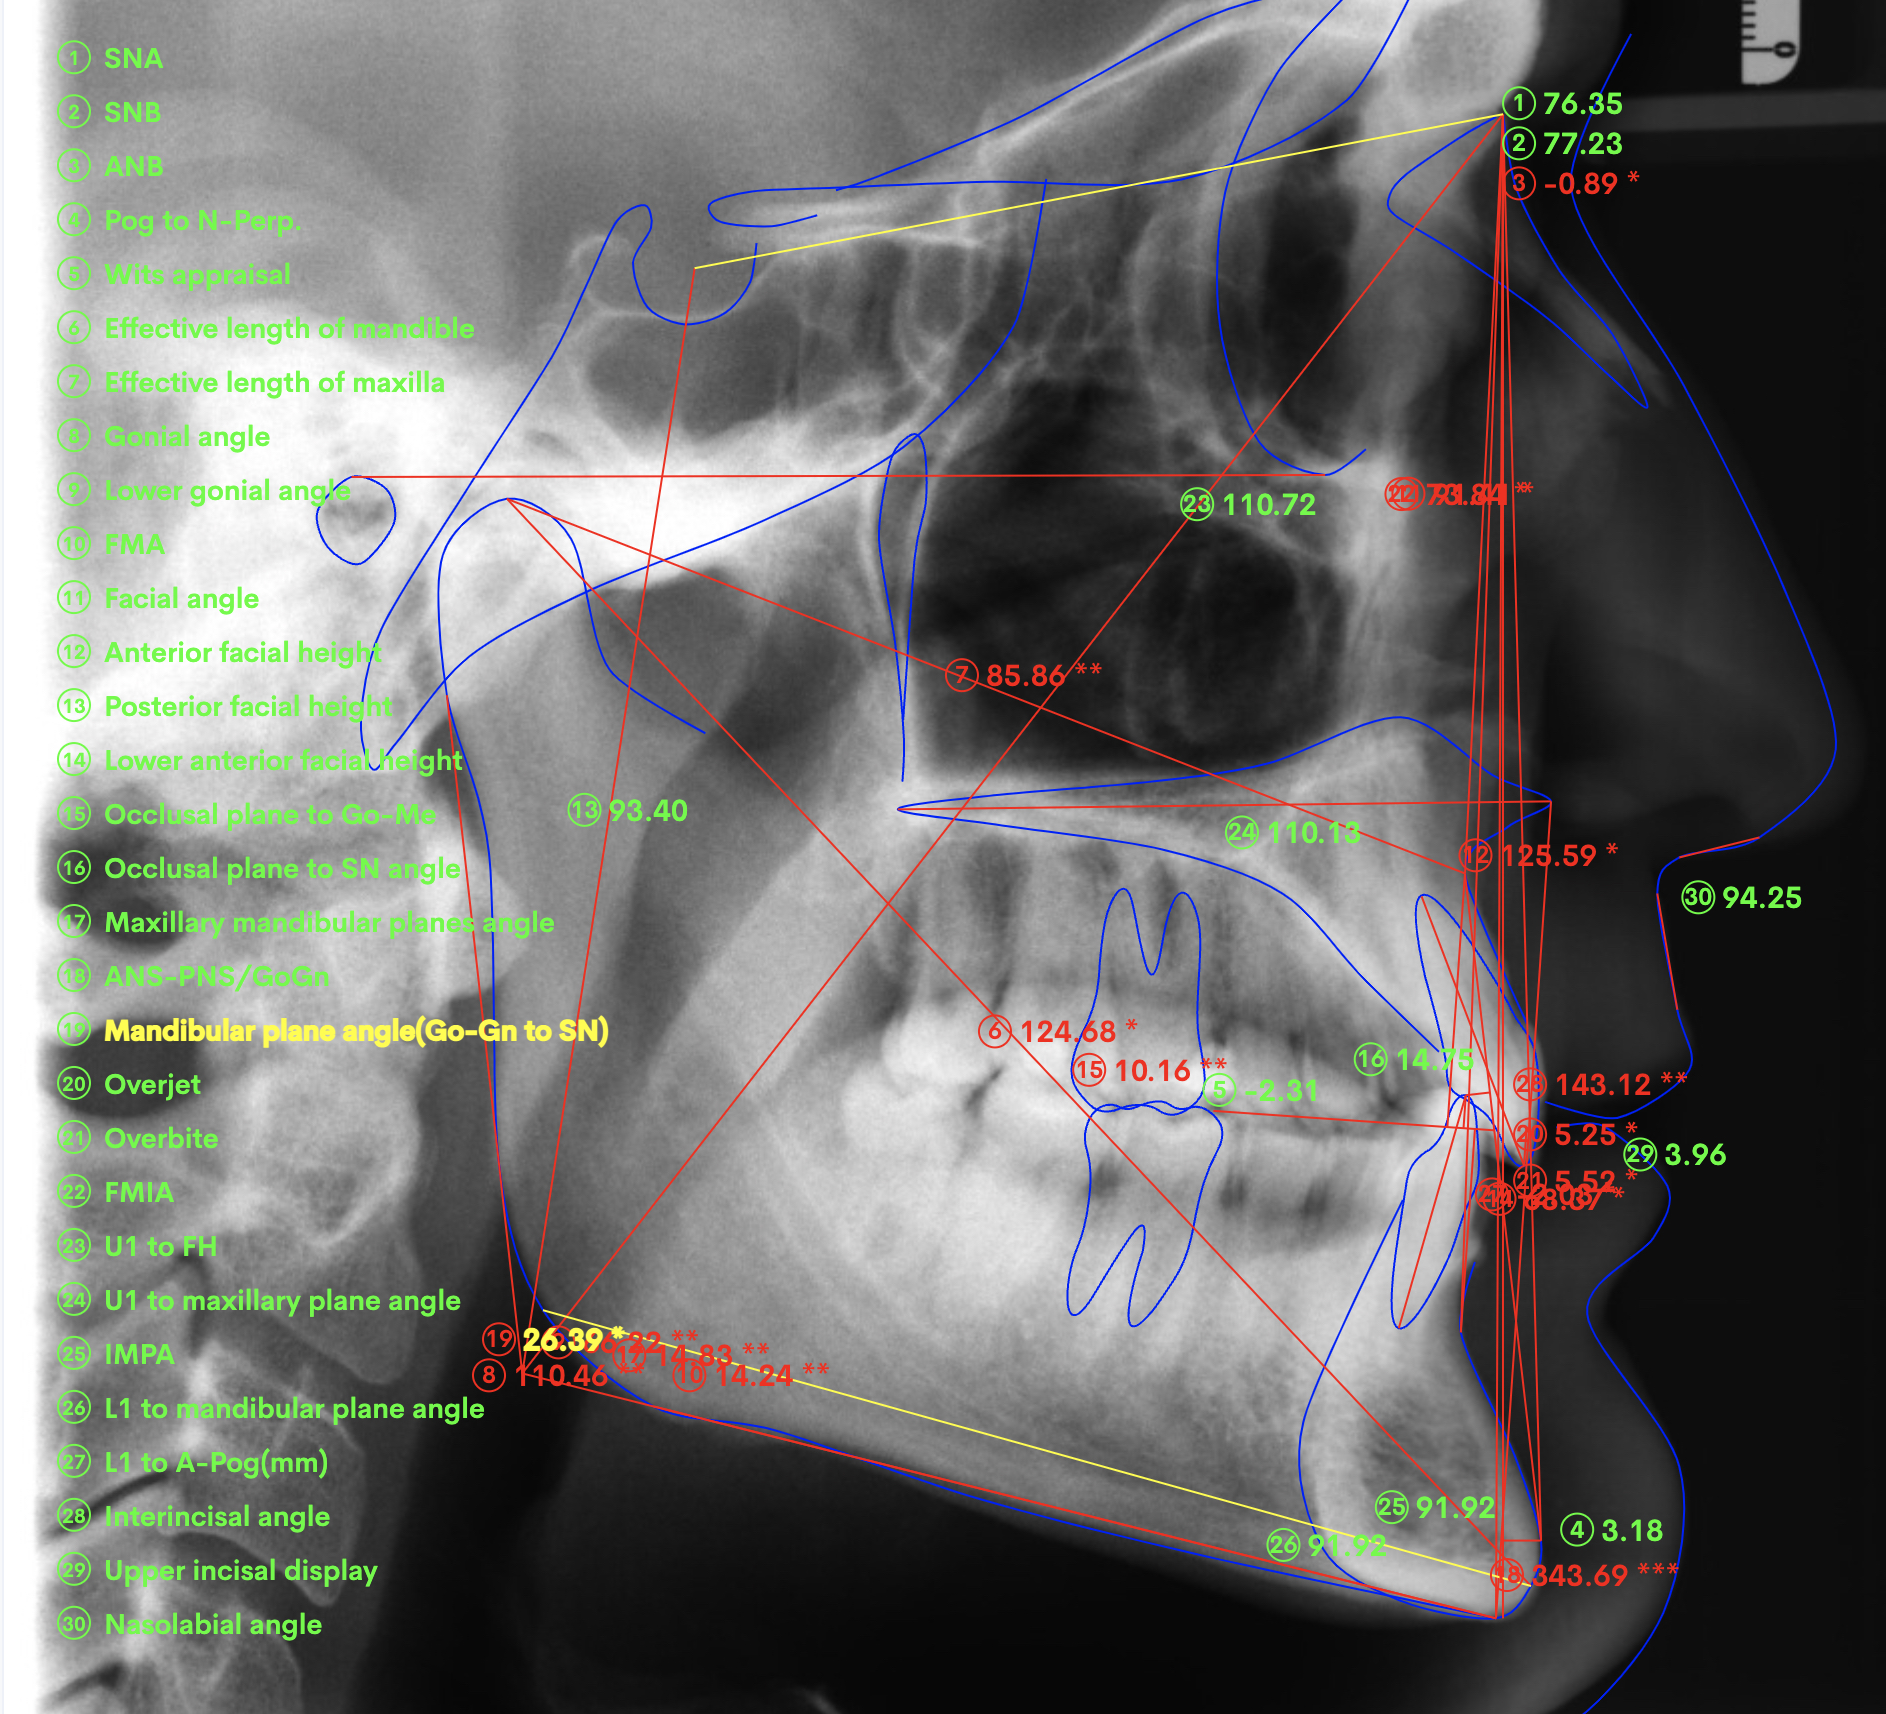

A 37-year-old male patient presented with the chief need for re establishing anterior alignment in both arches. Facial analysis showed a short face with a flat profile but proper chin projection (Figs. 9–12), and clinical examination revealed a skeletal Class I (ANB = 0.89°) and dental Class I malocclusion with severe deep bite (almost 100%), a deep curve of Spee, normal maxillary central incisor torque (Ui–FH = 110°), mild maxillary crowding and moderate mandibular crowding (Figs. 13–18). The deep bite components were represented in this patient by the severe skeletal condition of hypo divergent pattern (FMA = 14.24°) with normal maxillary and mandibular incisor inclination and decreased gonial angle (110.46°). Analysis of the cephalometric radiograph indicated a reduced lower anterior facial height, combined with a hypo-divergent pattern (Fig. 19). The only treatment option suggested was orthodontic treatment with aligners for deep bite correction with all the features described (bite ramps, pressure area, 3D curve of Spee levelling, Class II elastics and heavy occlusal contacts).

Fig. 19

At the end of the treatment, Class I canine and molar relationships were obtained, maxillary incisor inclination was slightly increased (Ui–FH = 112°), mandibular incisor inclination (IMPA = 97.09°) was fully corrected by means of proclination and the divergency was slightly increased (SN–GoGn = 27°) because of the relative posterior extrusion and use of Class II elastics—a small variation (1°), which is interesting considering the age of the patient (Figs. 25–35). A balanced smile arc was obtained with an ideal relationship between the maxillary incisors and lower lip, and torque control of the lateral and posterior segments generated a broader smile.

The superimposition of the cephalometric tracings showed some interesting changes induced by the orthodontic treatment (Figs. 36 & 37):

The maxillary incisor inclination with respect to the maxillary plane was reduced by about 2° (from 110° to 112°), and the mandibular incisor inclination with respect to the mandibular plane was reduced by about 6° (from 91° to 97°). There was a good inter-incisal relationship and sufficient symphysis support.

The relative extrusion of the maxillary and mandibular molars, combined with the use of bite ramps, generated a slight clockwise rotation of the mandible (SN–GoGn from 26° to 27°), which allowed a further improvement of the overbite.

The proclination of the maxillary and mandibular incisors improved the profile and support of the lip.